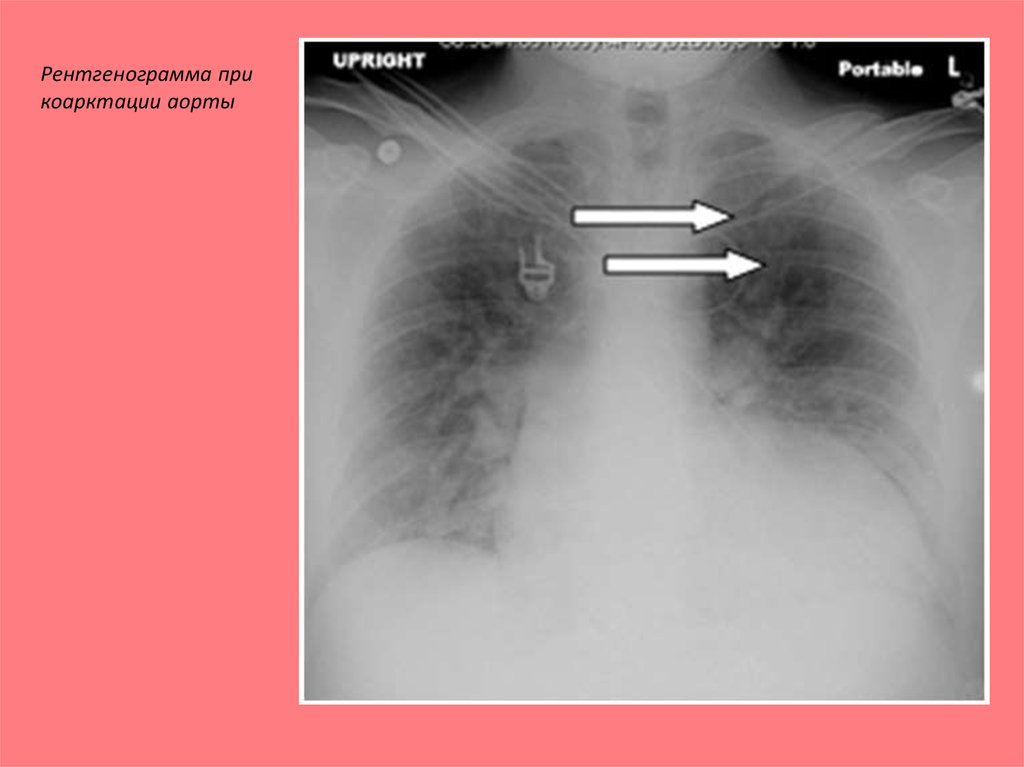

Рентгенограмма аорты

Рентгенограмма аорты 114 фотографий